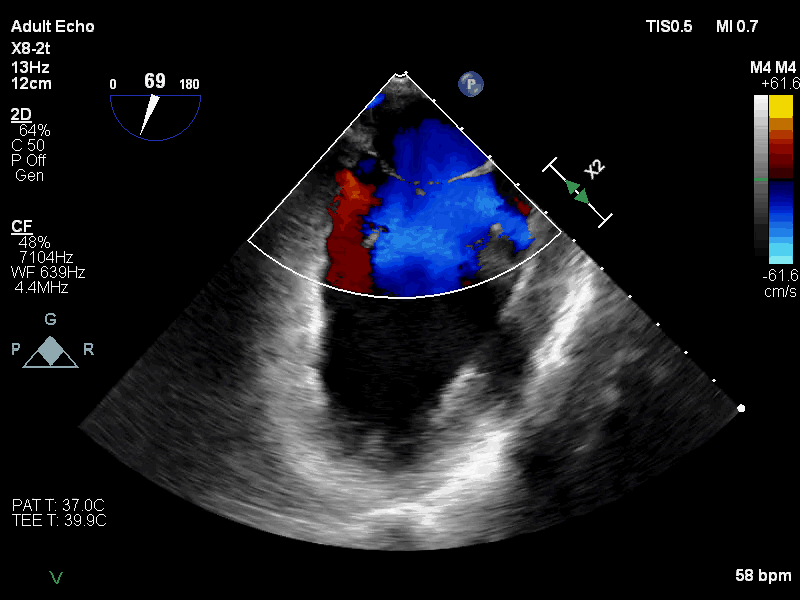

手术患者为一位高龄女性,多年来有间断发作的活动后心慌症状,近1年来患者胸闷气喘日益加重,呼吸困难,严重影响日常生活,于12月21日到武汉协和医院就诊,超声心动图检查显示二尖瓣口收缩期左房侧见大量反流信号;二尖瓣重度关闭不全;左心增大;左室收缩功能测值临界;心律失常。经武汉协和医院专家团队进行深入分析,反复讨论后最终决定采用国产二尖瓣瓣膜系统(TruDelta®)为患者进行微创介入二尖瓣置换术。

手术采用心尖入路,术中利用TEE引导确定心肌穿刺点,穿刺后导丝顺利跨二尖瓣进入左心房;TEE引导反复确认导丝未从腱索中穿过后,沿导丝推进输送系统,开始释放瓣膜;在二维和三维超声引导下完成同轴定位、D型定位后,完全释放瓣膜,撤出输送系统;最后根据血压调整瓣膜张力,进行心尖固定。

术后即刻超声心动图评估显示二尖瓣瓣膜释放位置精准,锚定稳固,无瓣周漏和中心反流,瓣膜工作形态良好,手术取得圆满成功。